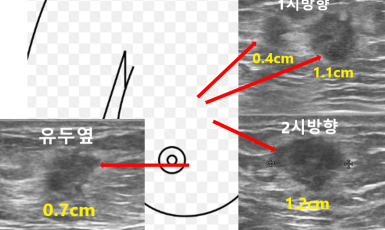

258번째 유방암 진단사례 (2019년8월12일) 대략 8개월전부터 오른쪽 유두에서 피가 섞인 유즙이 나왔었는데 별다른 검사없이 그냥 지내다 최근들어 양도 많아지고 가슴에 ..

작성자 레이디유 작성일 08-22 조회 6